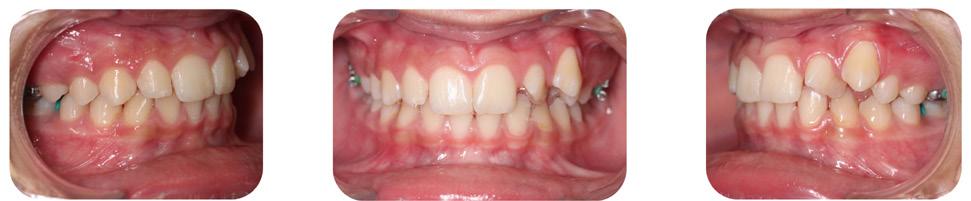

The patient was transferred to our office after 12 months of treatment with her previous clinician. She had a maxillary Hyrax, a mandibular Schwarz appliance and a partially bracketed upper arch with .022 x .028 Passive Self-Ligating (PSL) brackets (Carriere – Ortho organizers). The leveling arch wire was a .018 NiTi. The previous clinician proposed; transverse development, SWA and retention. The patient was already referred to an ENT for the evaluation of her airway. The authors explained to the patient and her mother that we may not be able to accommodate the maxillary cuspids and that odontectomy of two bicuspids may be necessary. We would, however, continue with the expansion protocol to its fullest capacity, utilize Straight Wire Appliances and add TADs to assist with translation of the maxillary cuspids. Class III elastics would be necessary and life-time retention of the dentition

following completion of the treatment. Composite add-ons were considered on maxillary lateral incisors, if required (Figure 3-A, B, C).

The maxillary cuspids were erupting mesially to the lateral incisors, with very little space to accommodate both teeth without an odontectomy. The expansion was continued (1/4 turn 2x per week), and an attempt was made to create more space for erupting cuspids with an open coil spring (OCS) – between the central incisors and the cuspids (Molar distalization spring, a .010 x .045 - Ortho Organizers). The OCS was measured and cut 4.0 mm longer than the available space. The maxillary arch wire was a .018 SS. An elastomeric chain (EC) was attached from the Hyrax to the lingual button on the lateral incisors. It was necessary to first pull the lateral incisors away from the alveolar process to prevent the break down of the buccal cortical bone around the cuspids (Figure

B, C).